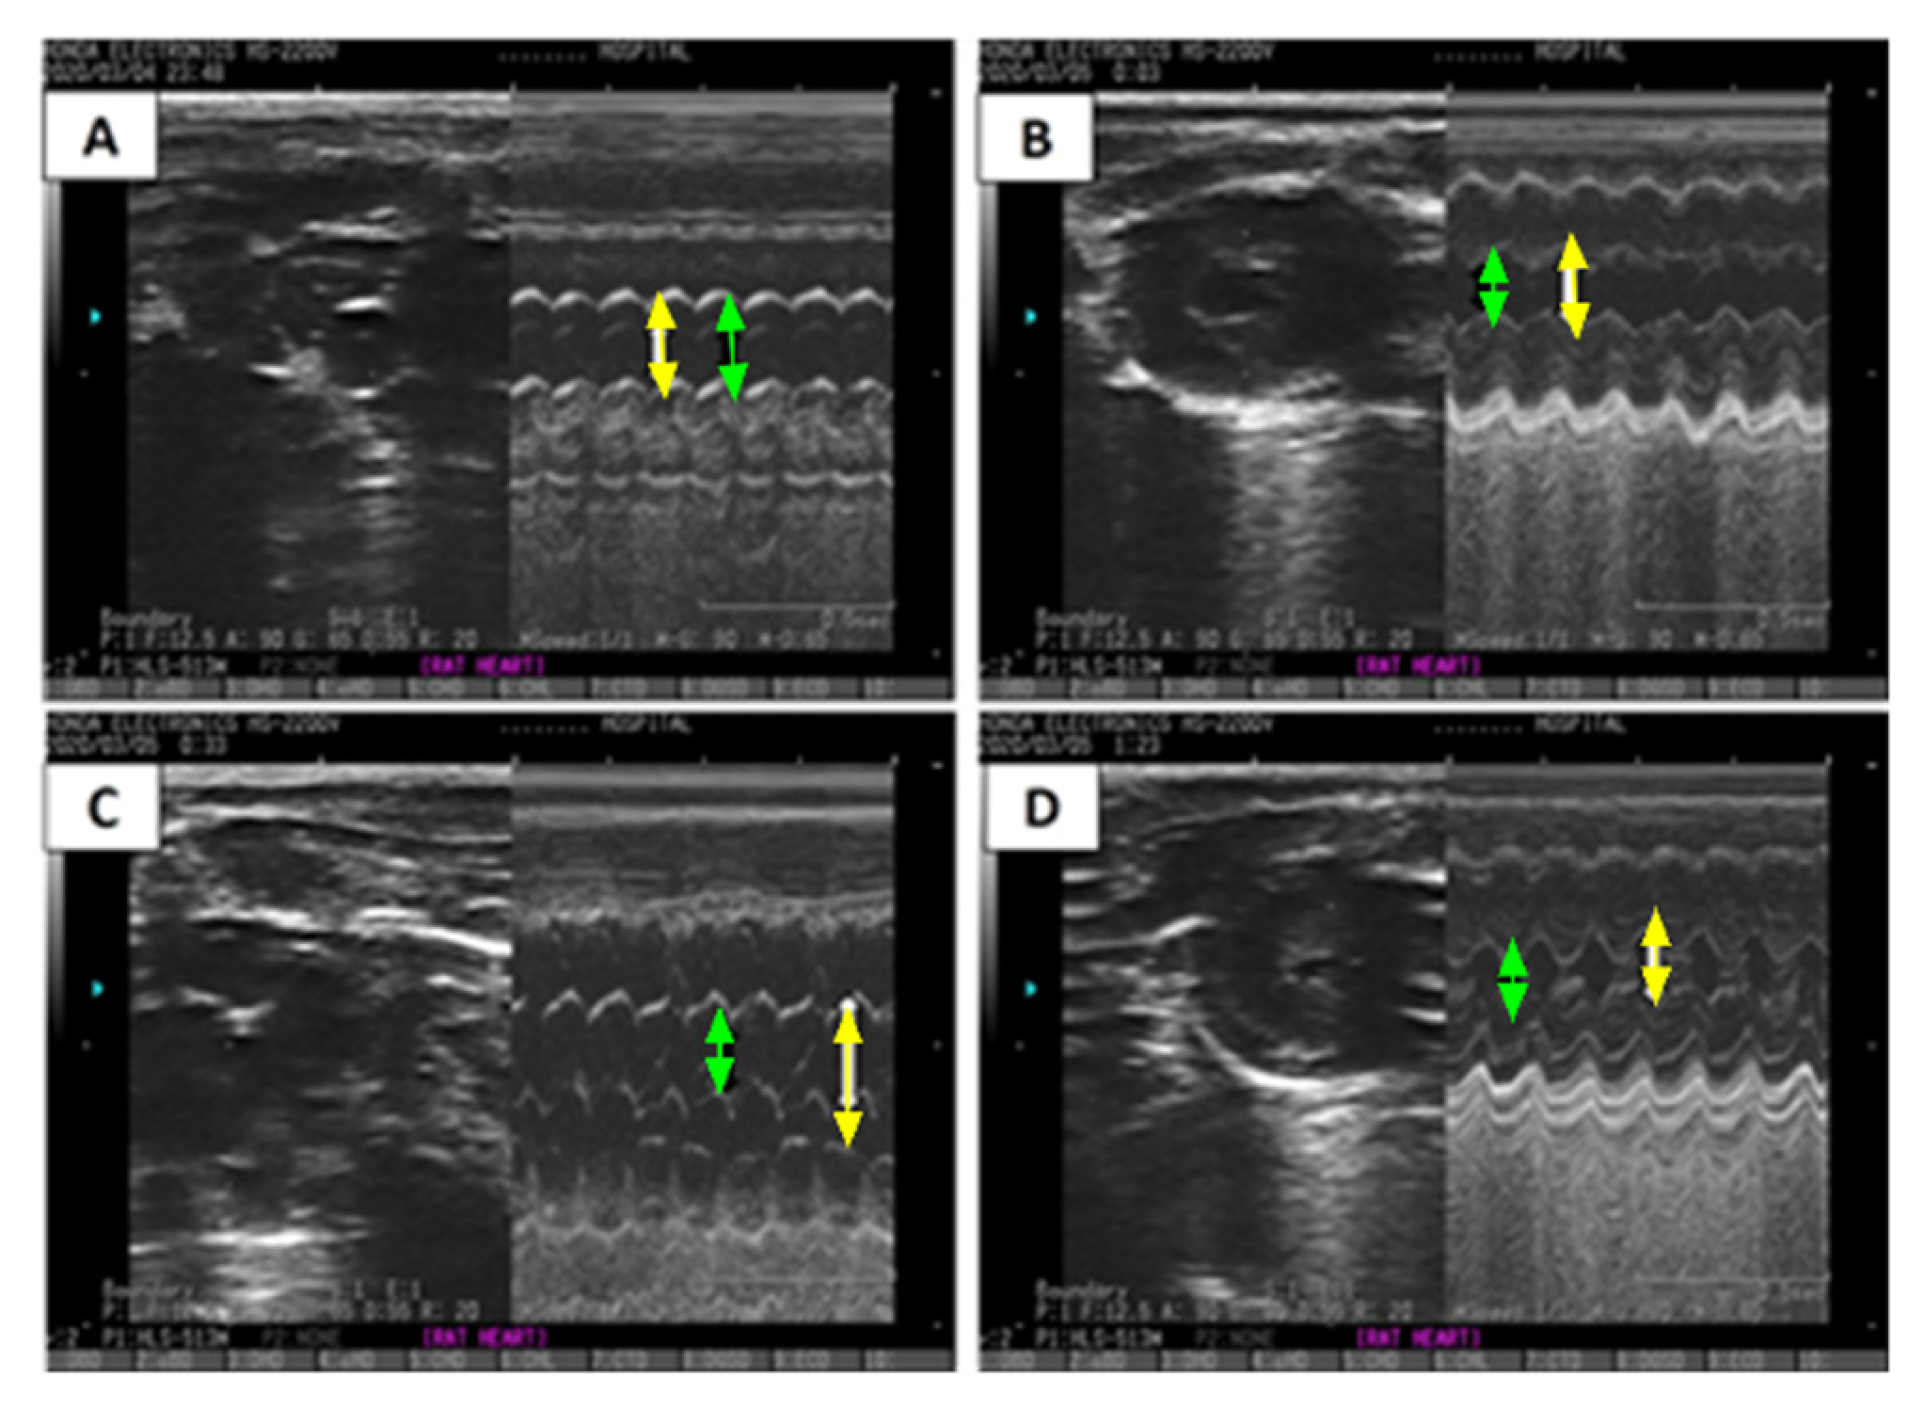

Additionally, an ECHO analysis was performed for verification, and images are presented in Table 2 and Figure 4. Figure 4 reveals a significant increase in left ventricular end-diastolic diameter (LVEDD) (1.30-fold) (p < 0.05), left ventricular end-systolic diameter (LVESD) (1.66-fold) (p < 0.05), and E/A ratio in the ISO-induced HF rat model (Table 2 and Figure 4C) compared to the saline/control rats (Table 2 and Figure 4A). Treatment with CCrP at a dose of 0.8 g/kg/day in the ISO-induced HF model reverted LVEDD and LVESD to normal conditions (Table 2, Figure 4C,D), with EF% values of 63.67% ± 0.13 comparable to the saline/control rats (Figure 3a). Furthermore, healthy rats that received CCrP at a dose of 0.8 g/kg/day for 14 days showed normal LVEDD (7.93 ± 0.03) and LVESD (5.53 ± 0.09) comparable to those seen in the saline/control rats, suggesting a lack o-*f heart toxicity due to CCrP administration (Figure 4B).

Figure 4. ECHO images demonstrate the effect of CCrP on ISO-induced changes in M-mode in LVEDD (yellow arrow) and LVESD (green arrow). Groups include saline/control (A), CCrP/control (B), ISO/saline (C), and ISO + CCrP (D). CCrP at a dose of 0.8 g/kg/day. ISO: isoproterenol; CCrP: cyclocreatine phosphate; LVEDD: left ventricular end-diastolic diameter; and LVESD: left ventricular end-systolic diameter.

Table 2. After 14 days, ISO/CCrP rats showed normal LVEDD and LVESD, while ISO/saline rats showed a significant increase. * p < 0.05 for ISO/saline vs. saline/control rats, and # p < 0.05 for ISO/CCrP vs. ISO/saline rats.

GroupLVEDD (mm)LVESD (mm)

Saline control7.77 ± 0.155.43 ± 0.03

ISO + saline10.07 ± 0.12 *9.00 ± 0.15 *

ISO + CCrP8.03 ± 0.09 #6.27 ± 0.07 #